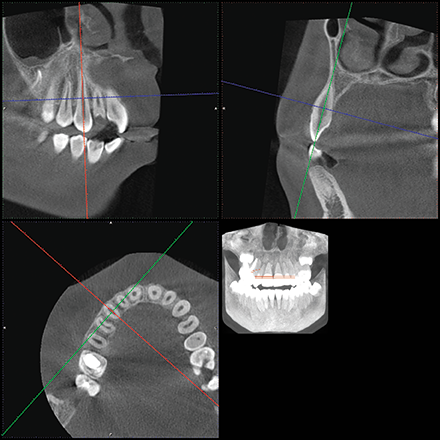

CBCT analysis revealed limited alveolar boundaries on the buccal and lingual of the mandibular anterior teeth (Fig. 3).

Fig. 3 Fig. 4